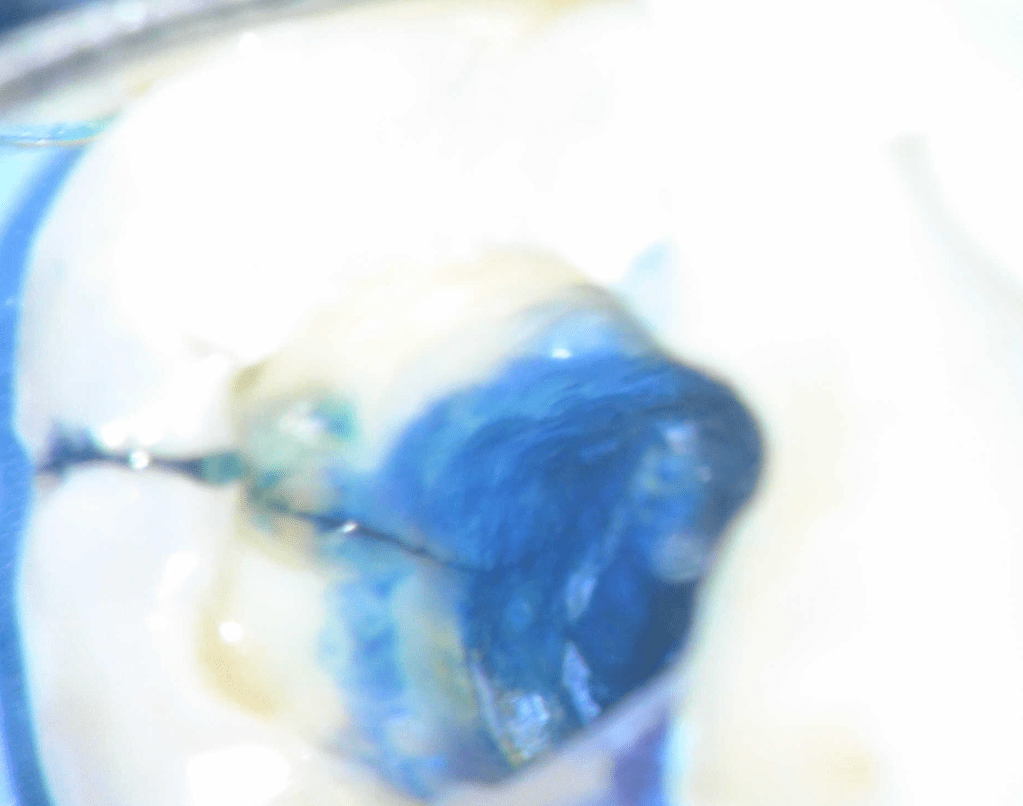

Fisura, remoción amalgama para explorar